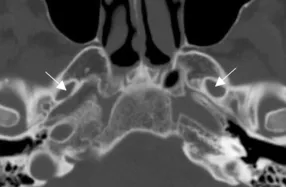

A Steady-state free precession (SSFP) axial image showing the olfactory nerves (arrows).

A Steady-state free precession (SSFP) axial image showing the optic nerves (arrows).